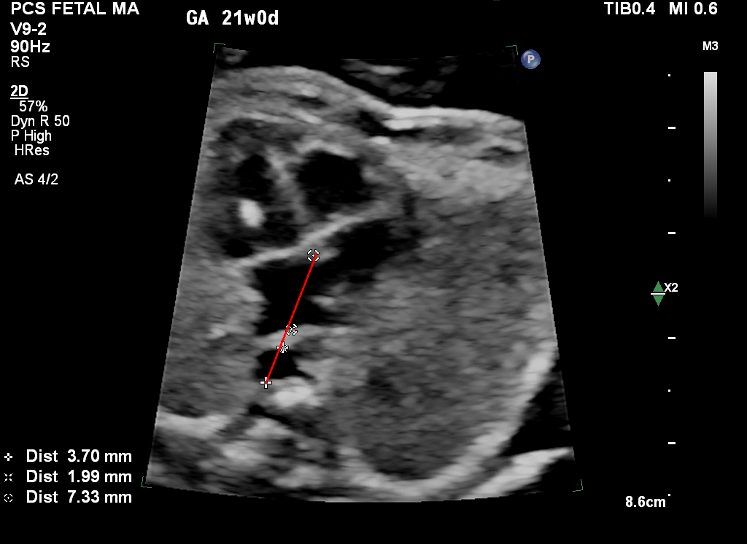

Post-LA Space Index

This index measures the distance between the LA and descending aorta, with higher values suggesting TAPVC. Studies show remarkable sensitivity and specificity with this method.

Measurement should be made in the line connecting the DTA diameter with the crux of the heart.